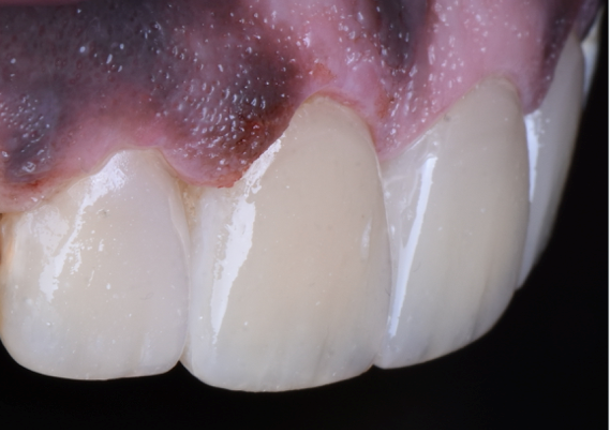

After

Step 8 – Post operative view Highly aesthetic outcome using (ceram.x® duo).

Material and Method The digital smile design approach is very beneficial in deciding the preferred ideal outcome. Interpretation was onto the diagnostic wax up. After isolation with the rubber dam, caries excavation and cavity preparation was performed. Teeth were etched with DeTrey® Conditioner 36rinsed and dried. Prime&Bond universalTM was applied and light-cured. Reconstructions were made with (ceram.x® duo) using a multi-layering technique with dentin shade (ceram.x® duo D3) and enamel shade (ceram.x® duo E2). For finishing& polishing firstly finished with a diamond bur, then with Enhance® Finishing System and Polishing with Enhance® PoGo system and Prisma Gloss® pastes.

Re-creating an aesthetic smile was a challenging task in the present case. The final restoration satisfied the patient's expectations. Ceram.x® duo showed a remarkable final natural appearance in this case. Ceram.x® duo has excellent handling, finishing, and polishing properties that resulted in a highly aesthetic outcome.